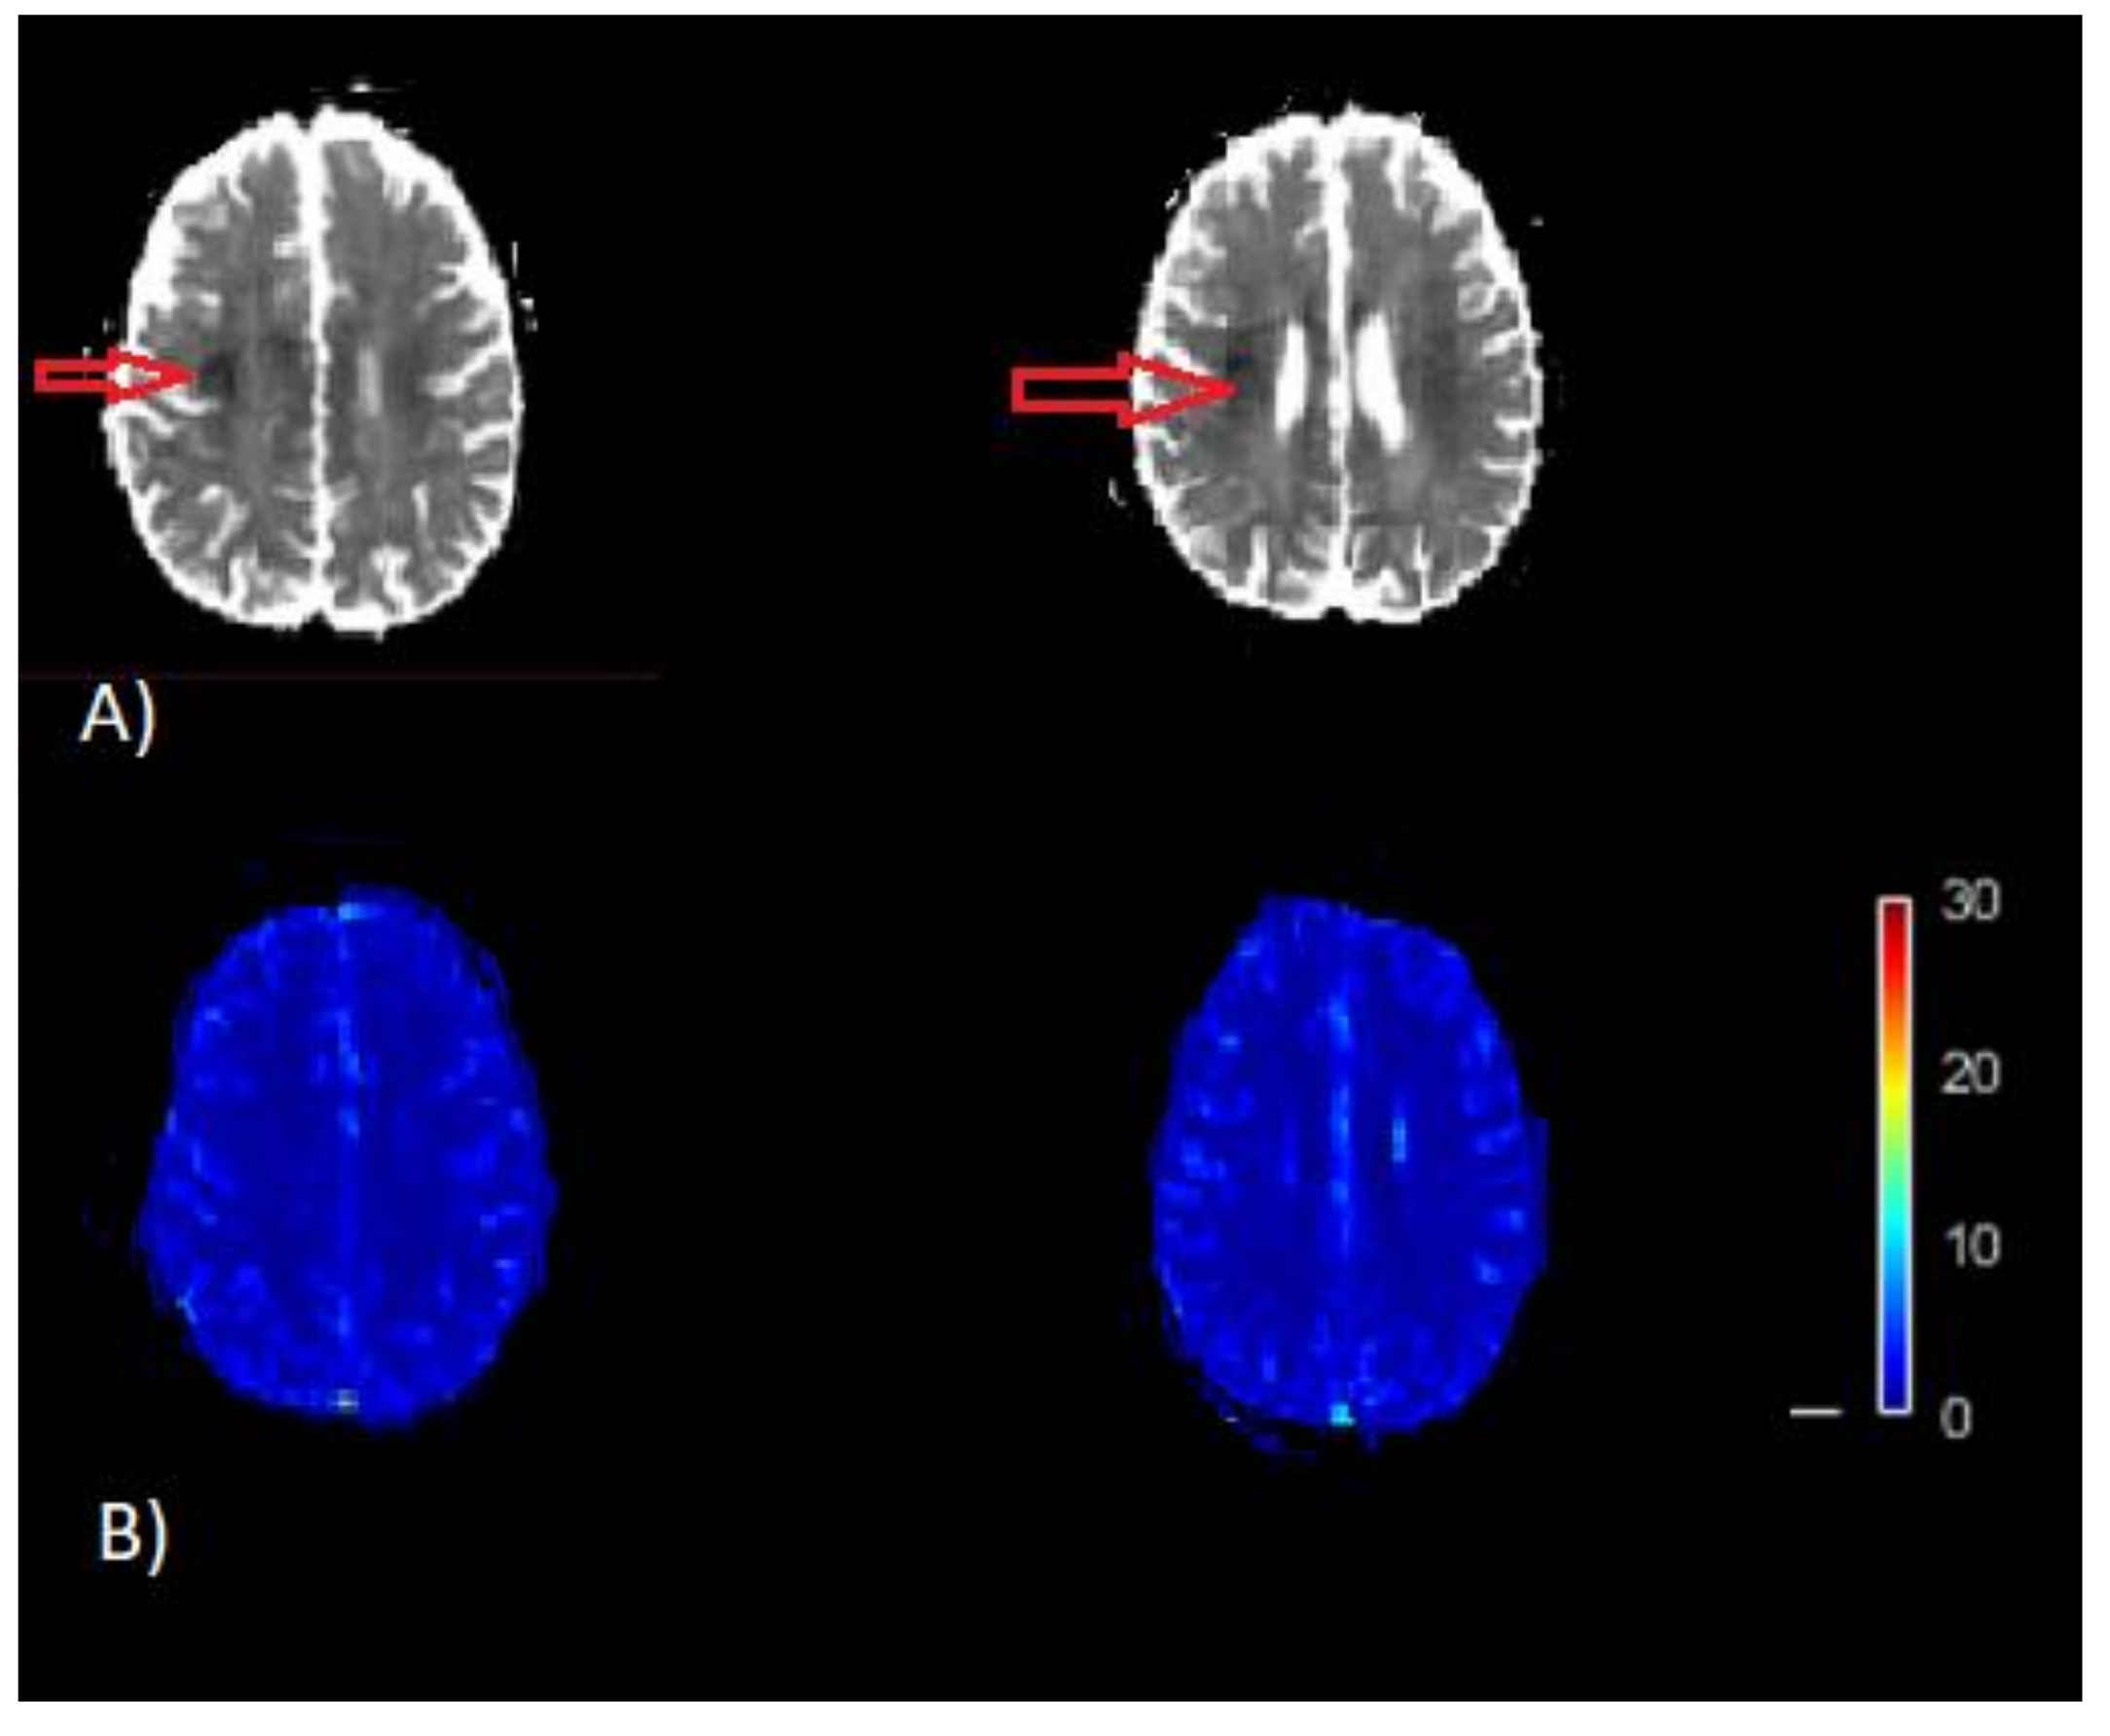

The perfusion model uses AIF as an initial input to calculate perfusion parameters as final output [10]. In the process of calculation of perfusion imaging parameters, the PVE seriously affects the estimation of arterial input function (AIF) [11,12,13,14,15,16]. As voxels with signals from both artery and surrounding tissues may result in distortion of the signal loss of the contrastive agent during the passage of blood, this may lead to erroneous estimation of AIF, which consequently yields misleading brain maps of CBF and Tmax. In current clinical practices, volumes on brain image with Tmax greater than 6 s are considered to be the critically hypoperfused region, which is also known as the penumbra, and tissues with relative CBF <30% are considered to be the infarct core [17]. Misleading CBF and Tmax brain images may fail to identify infract regions as well as hypoperfused regions (Figure 1). Early and correct assessment of the hypoperfused as well as infract regions are critical for appropriate diagnosis and treatment decisions in acute stroke [11,16,17].

Figure 1.

Example of misleading perfusion parameter maps. (A) Apparent diffusion coefficient (ADC) image (/s). The dark region on ADC image thresholded by ADC ≤ 620 × 10−6 /s is the infracted core (red arrow) on the map. (B) CBF map (bottom) [mL/100 g/min]. This CBF map does not indicates the infract region as represented on the ADC map, which is a result of inaccurate quantification of CBF.